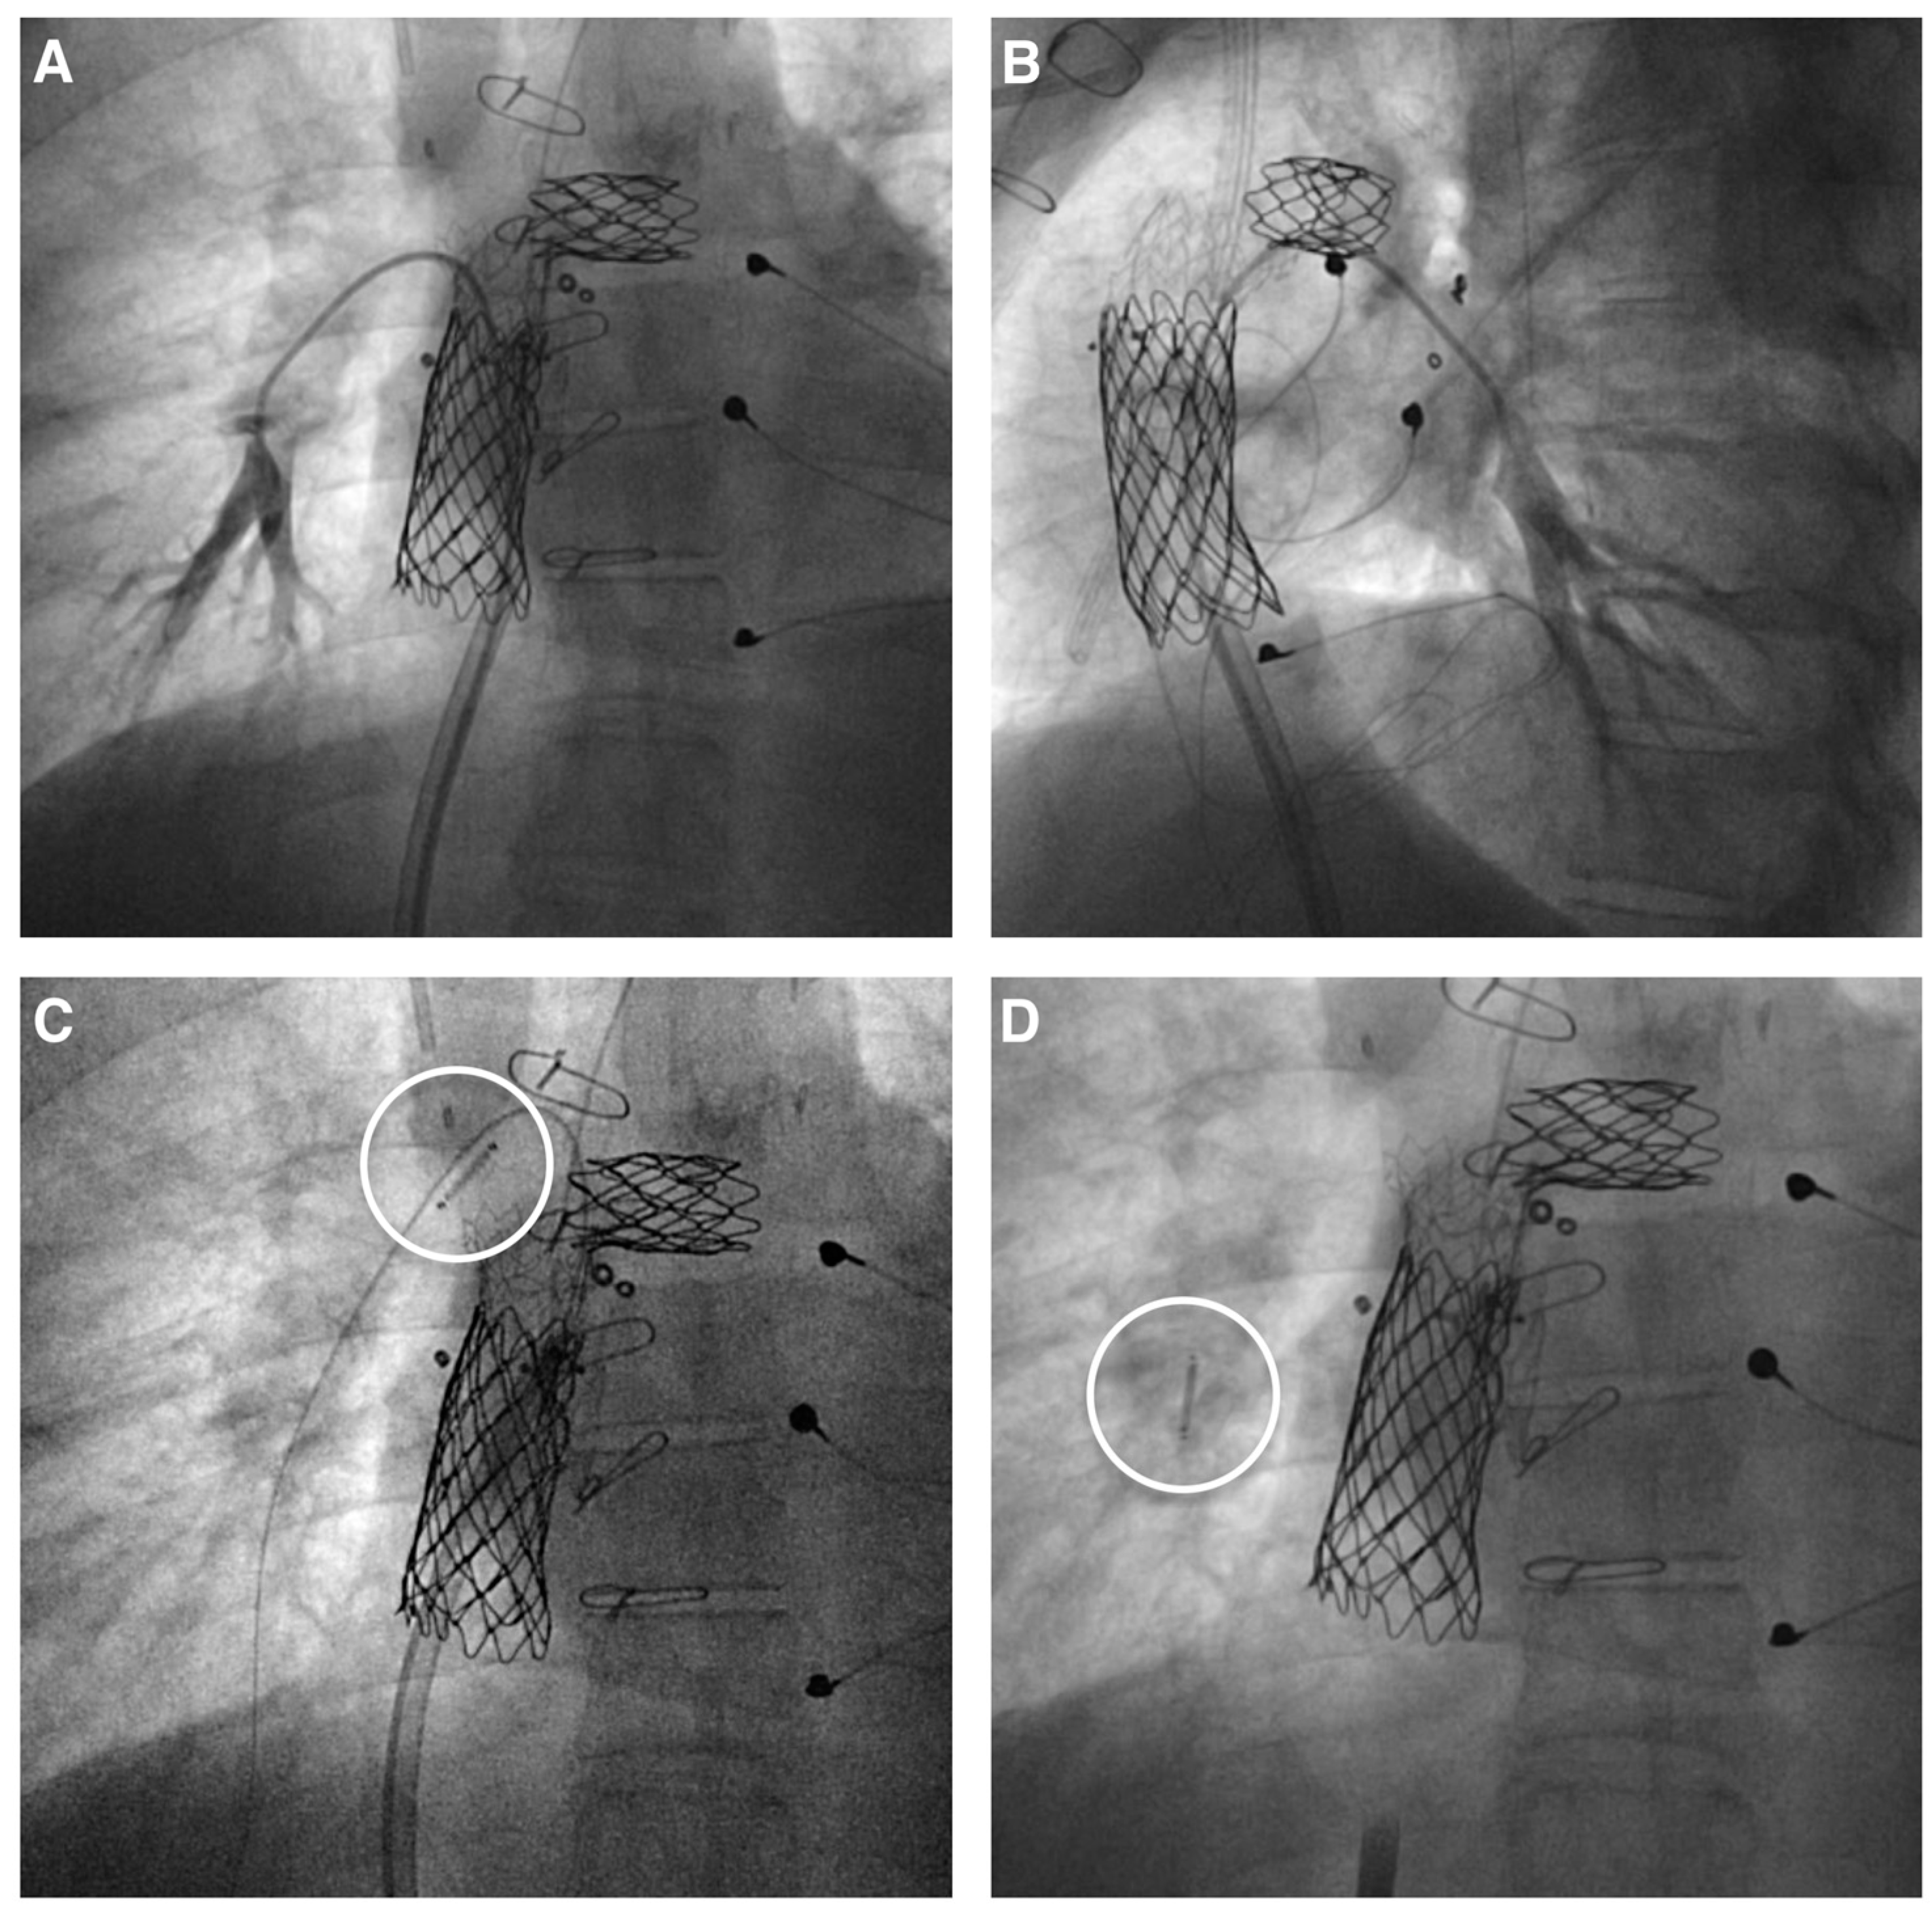

Figure 2.

CardioMEMS implantation in Fontan patients. (A,B) A 7–8 mm right lower pulmonary artery branch is selected to accommodate the CardioMEMS device in a patient with a Fontan circulation who previously underwent conduit and left pulmonary artery stenting. (C) The device (white circle) is advanced over a 0.018″ wire, aided by a 12 French long sheath in the stented Fontan conduit. (D) The CardioMEMS device (white circle) in place after release in the selected pulmonary artery branch.